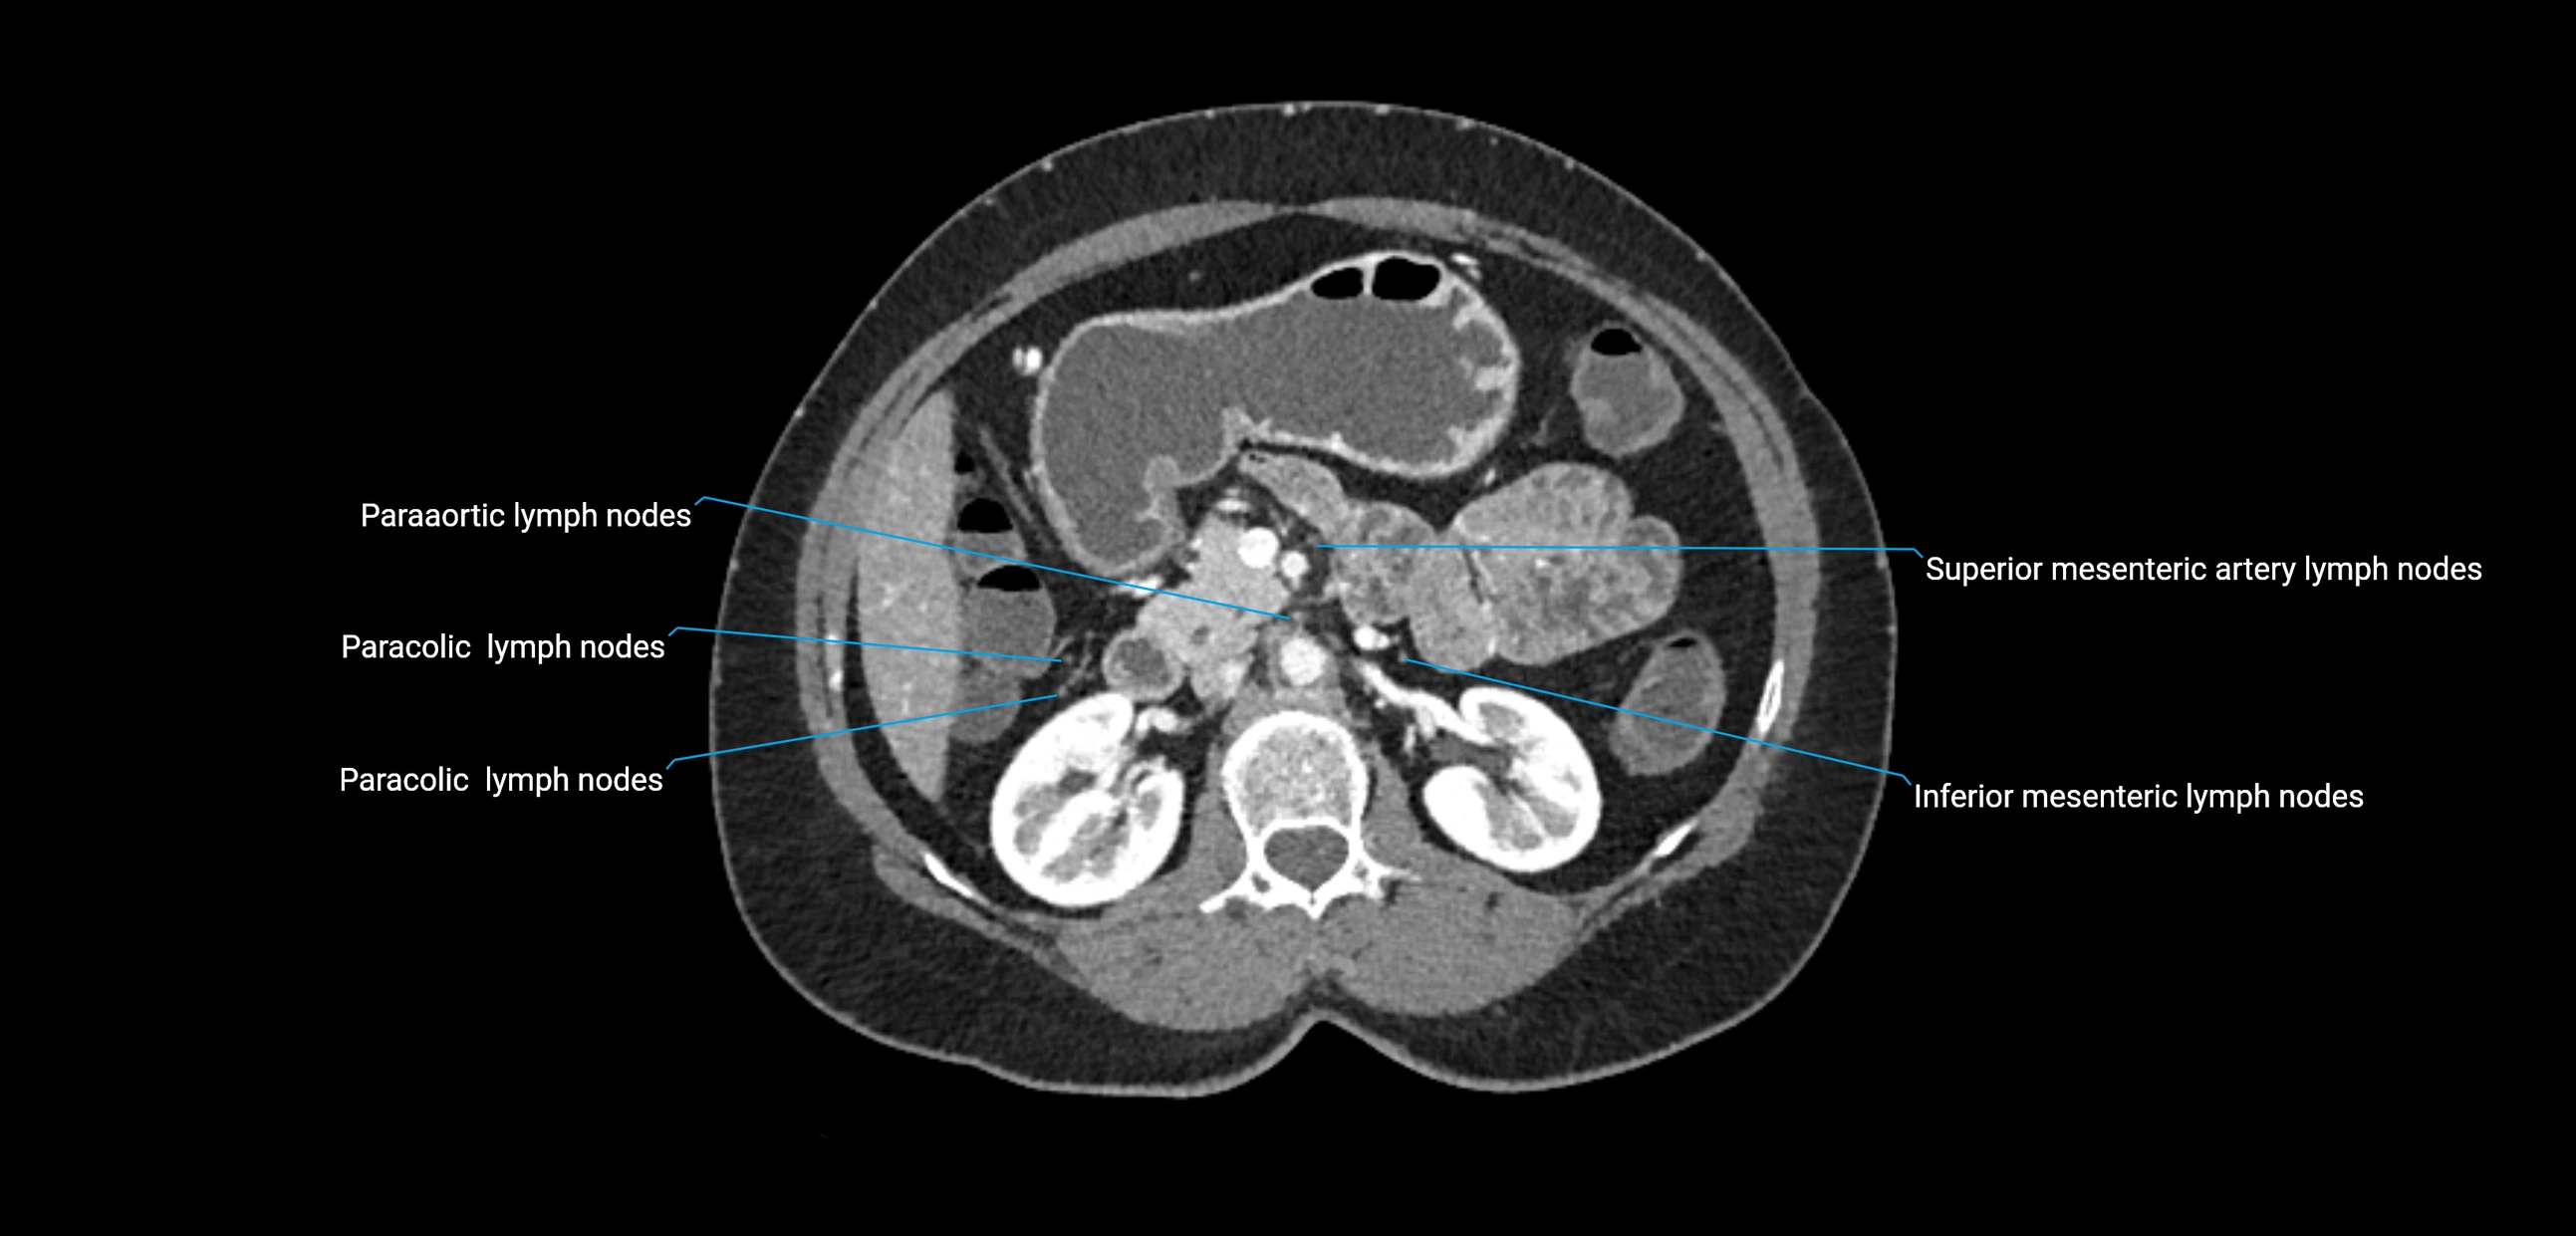

CT image

image